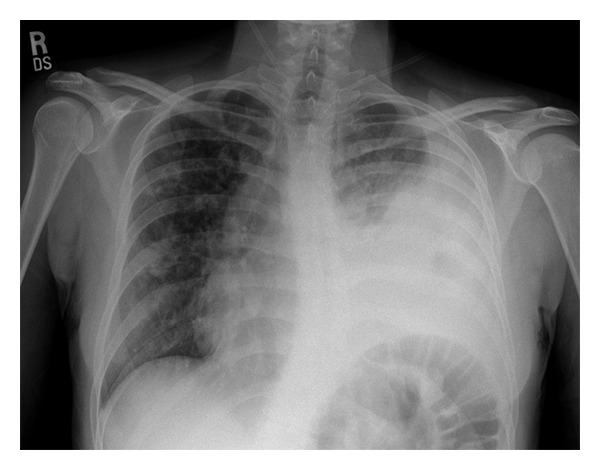

Input 3: What is seen in the X-ray and what should be done?

Image: